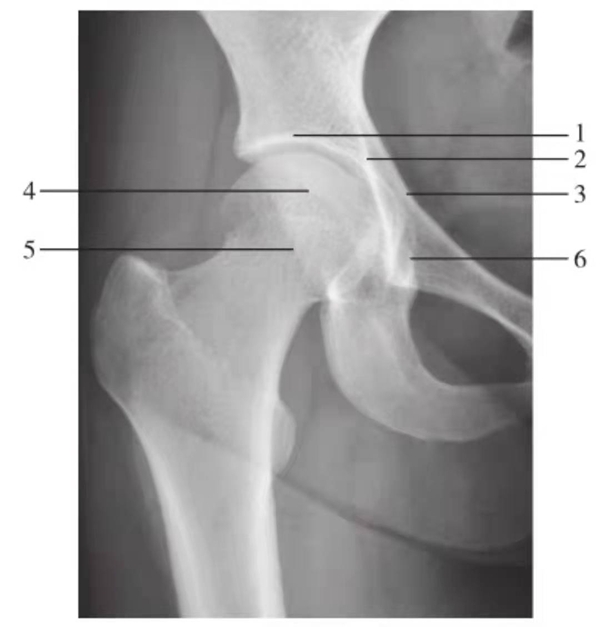

图2 髋关节正位片(成人期)

1.髋臼线;2.髂坐线;3.髂耻线;4.前唇线;5.后唇线;6.泪滴